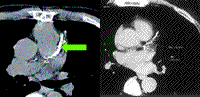

对有症状患者,可先采用CAC检测有效排除,以决定是否需行有创检查或住院治疗。CAC积分若<100,核素负荷试验检出血管异常灌注可能性低于2%,心导管检出显著血管阻塞(狭窄超过50%)可能性低于3%。快速CT检测CAC预测冠状动脉疾病(CAD)血管阻塞(狭窄超过50%)敏感性高达95%~99%,但特异性有限。超过7600例有症状患者的CAC研究表明,无CAC(积分=0)者无阻塞性血管疾病的可信度非常高,其阴性预测值为96%~100%。

直接比较研究发现,对有症状患者,通过CAC检出阻塞性CAD的作用与放射性核素运动试验相当。对可运动的有症状患者,鉴于运动能力可提供有效的预后信息,因此采用已有检查手段比快速CT检查效果好。心脏CT(有对比的CT血管造影或无对比的CAC评估)等结构性检查应作为二线检查,只有在功能性检查不允许或不能确诊时才采用。患者服用药物、运动能力、基线室壁运动或心电图异常不影响CAC检测准确性。